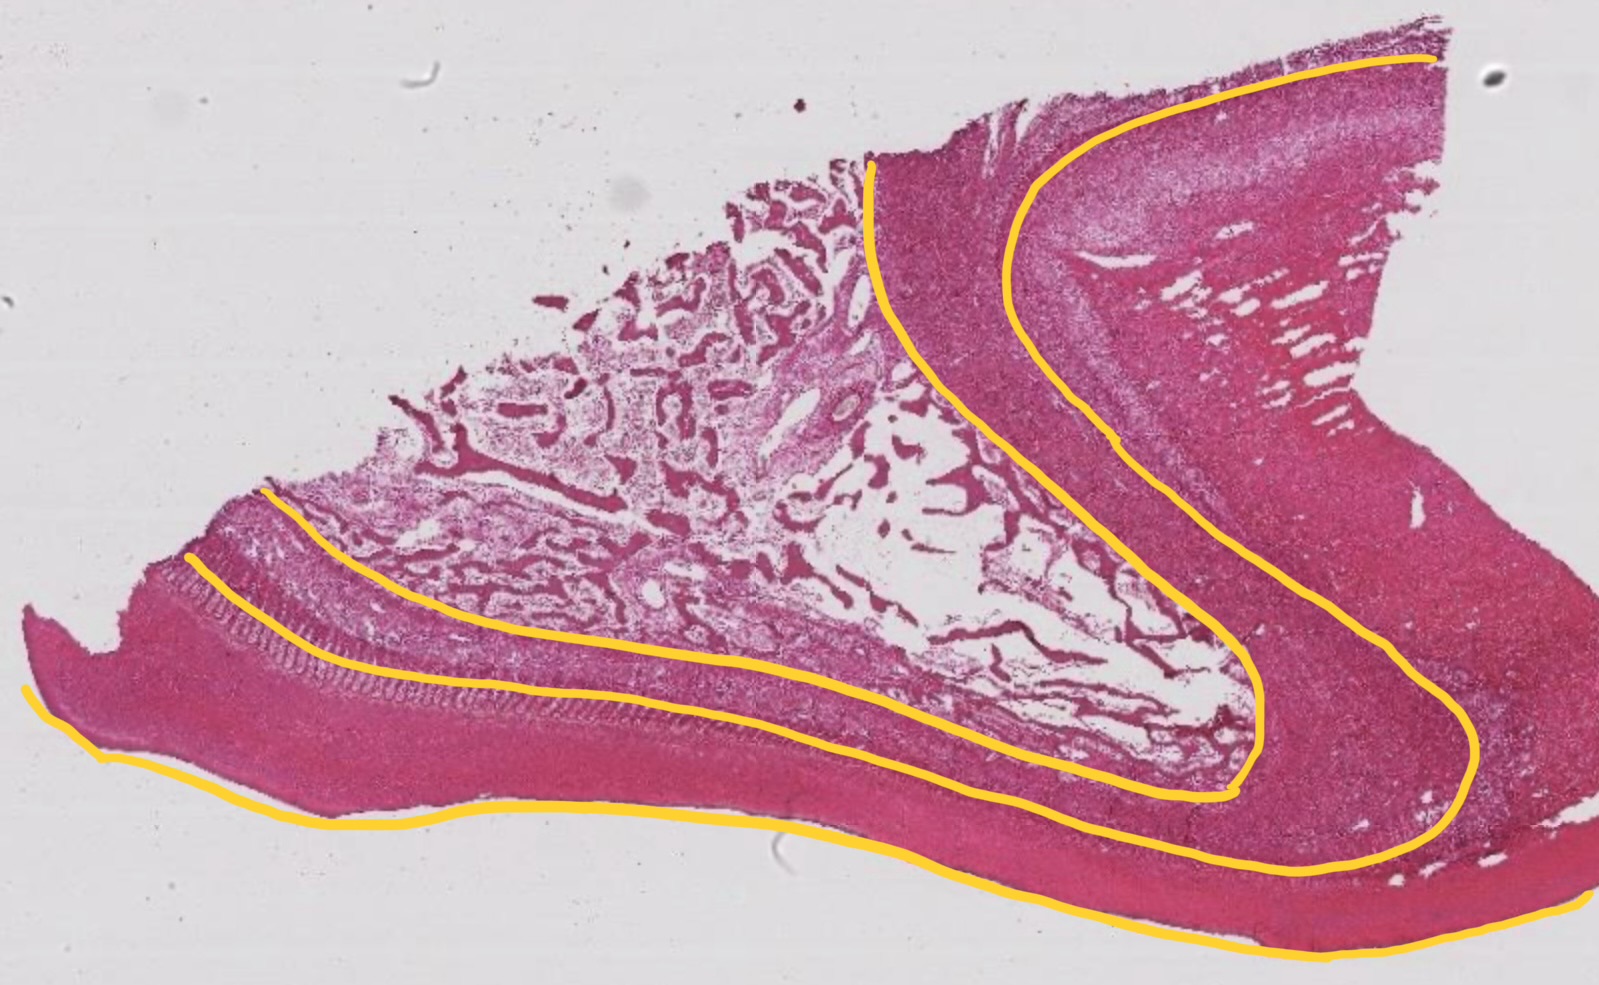

laminitis

occurs when the lamina tears away from the hoof wall

secondary epidermal lamellae elongate to a point (normally rounded)

pointed tip and basement membrane separate from basal cells of the primary dermal lamellae

leukocytes infiltrate dermis and empty basement membrane of the secondary epidermal lamellae